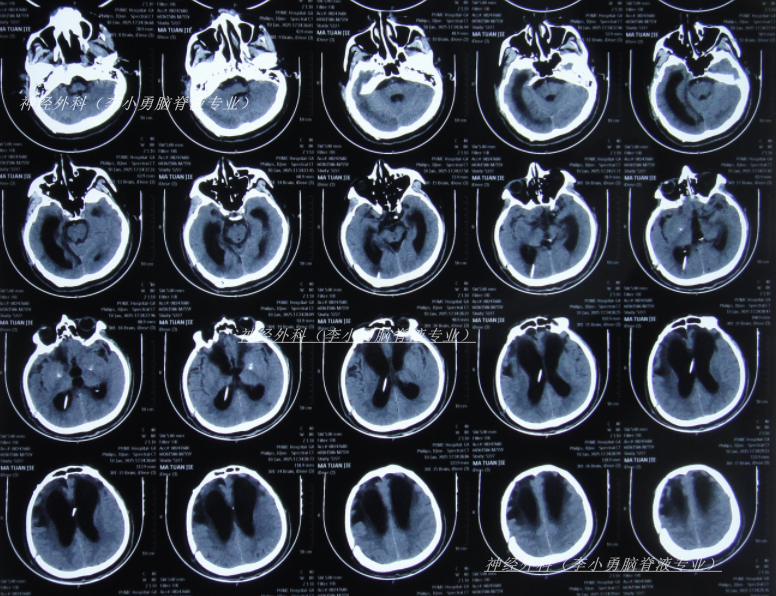

脑室腹腔分流术后13天即2024年10月2日,查头颅CT示去骨瓣术后,脑室分流术后状态,脑室仍有扩张(图-1);但意识有好转。

图-1:2024年10月2日头颅CT

脑室腹腔分流术后22天即2024年10月11日,查头颅CT示脑室缩小(图-2)。

图-2:2024年10月11日头颅CT